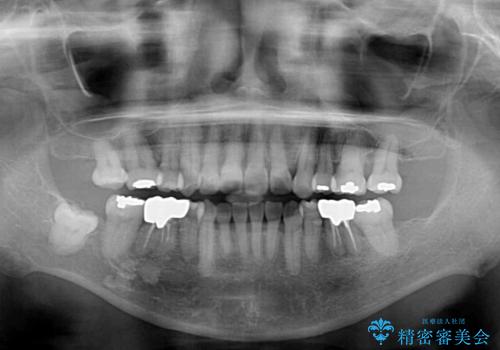

- 八重歯やクロスバイトを気にして来院された患者様です。

口元の突出感はありませんでしたが、デコボコが強く、非抜歯矯正とすると出っ歯仕上がりとなる可能性があったため、上下左右の第一小臼歯4本を抜歯し、ワイヤー装置にて矯正治療を行うこととしました。

抜歯矯正により口元が引っ込みすぎて、ほうれい線が顕著となるのではないかと心配しておりましたが、矯正後にほうれい線が気になることはなく、口元もすっきりとした感じになりました。